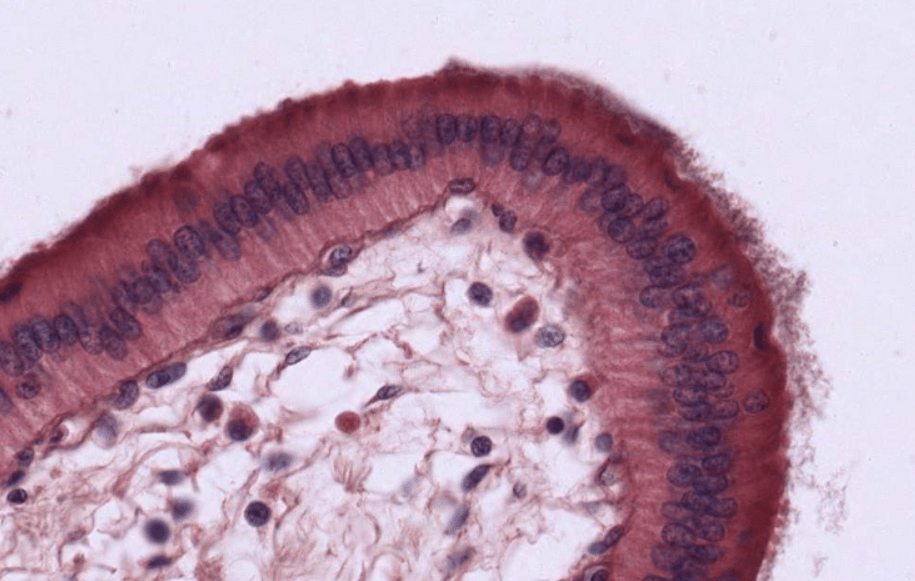

VESÍCULA BILIAR

Epitelio cilíndrico simple con microvellosidades, vesícula biliar de humano.Vesícula biliar de mono.Vesícula biliar de humano, HyE.Los pliegues irregulares de la mucosa forma los senos de Rokitansky–Aschoff. (estrella)Identifique el epitelio que recubre la muscosa de la vesícula biliar.La vesícula biliar es un órgano que carece de capa submucosa.Vesícula biliar, HyE.